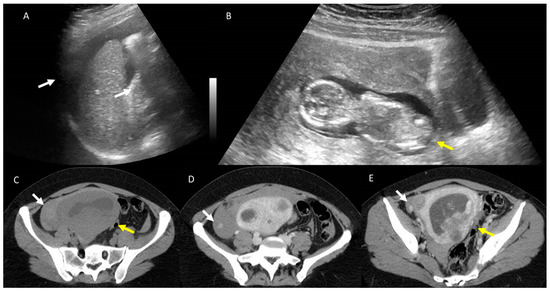

4. Clinical Setting: Abdominal Pain

5. Acute Appendicitis

6. Biliary Tract and Pancreatic Diseases